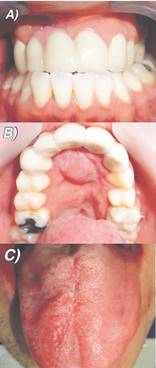

Una vez realizado el injerto, se realiza el retiro de aparatología fija de ortodoncia y la coordinación para el inicio de la rehabilitación estética mediante prótesis fija plural, la cual utiliza como pilares las piezas 1.3, 2.1 y 2.2 para rehabilitar las piezas 1.2 y 1.1. Esto busca, además, mejorar la anatomía dentaria de los incisivos centrales superiores derecho e izquierdo y a su vez, mejorar la estética de todo el sector anterior.

Luego del procedimiento quirúrgico y tras realizar los controles postoperatorios, se ha observado una mantención y estabilidad del injerto en la zona de la fístula desde el momento de la cirugía a la fecha. Además, se ha producido una notable mejoría en el habla (al mejorar la IVF 9 a una IVF 2) y alimentación del paciente, influyendo positivamente en sus relaciones interpersonales y autoestima.